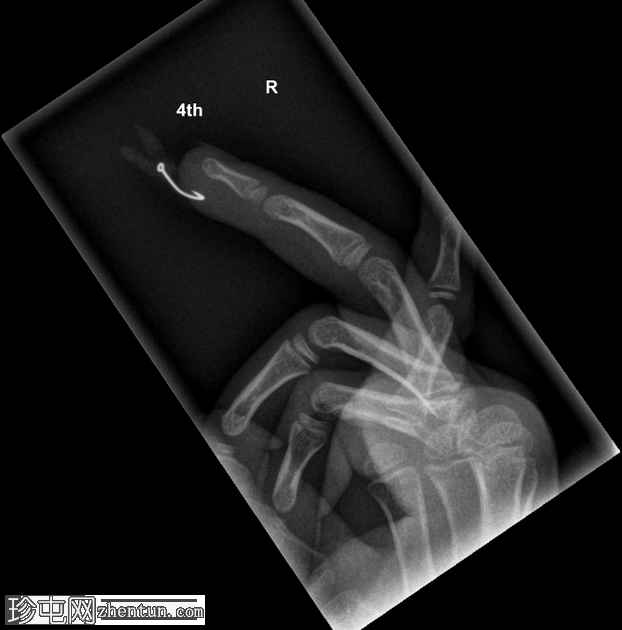

年龄:5岁

性别:男

右手无名指

X光片

侧位片

鱼钩异物,附有蛆虫。

鱼钩异物较为常见,但像本例中鱼钩上还附着蛆虫的情况则较为罕见!